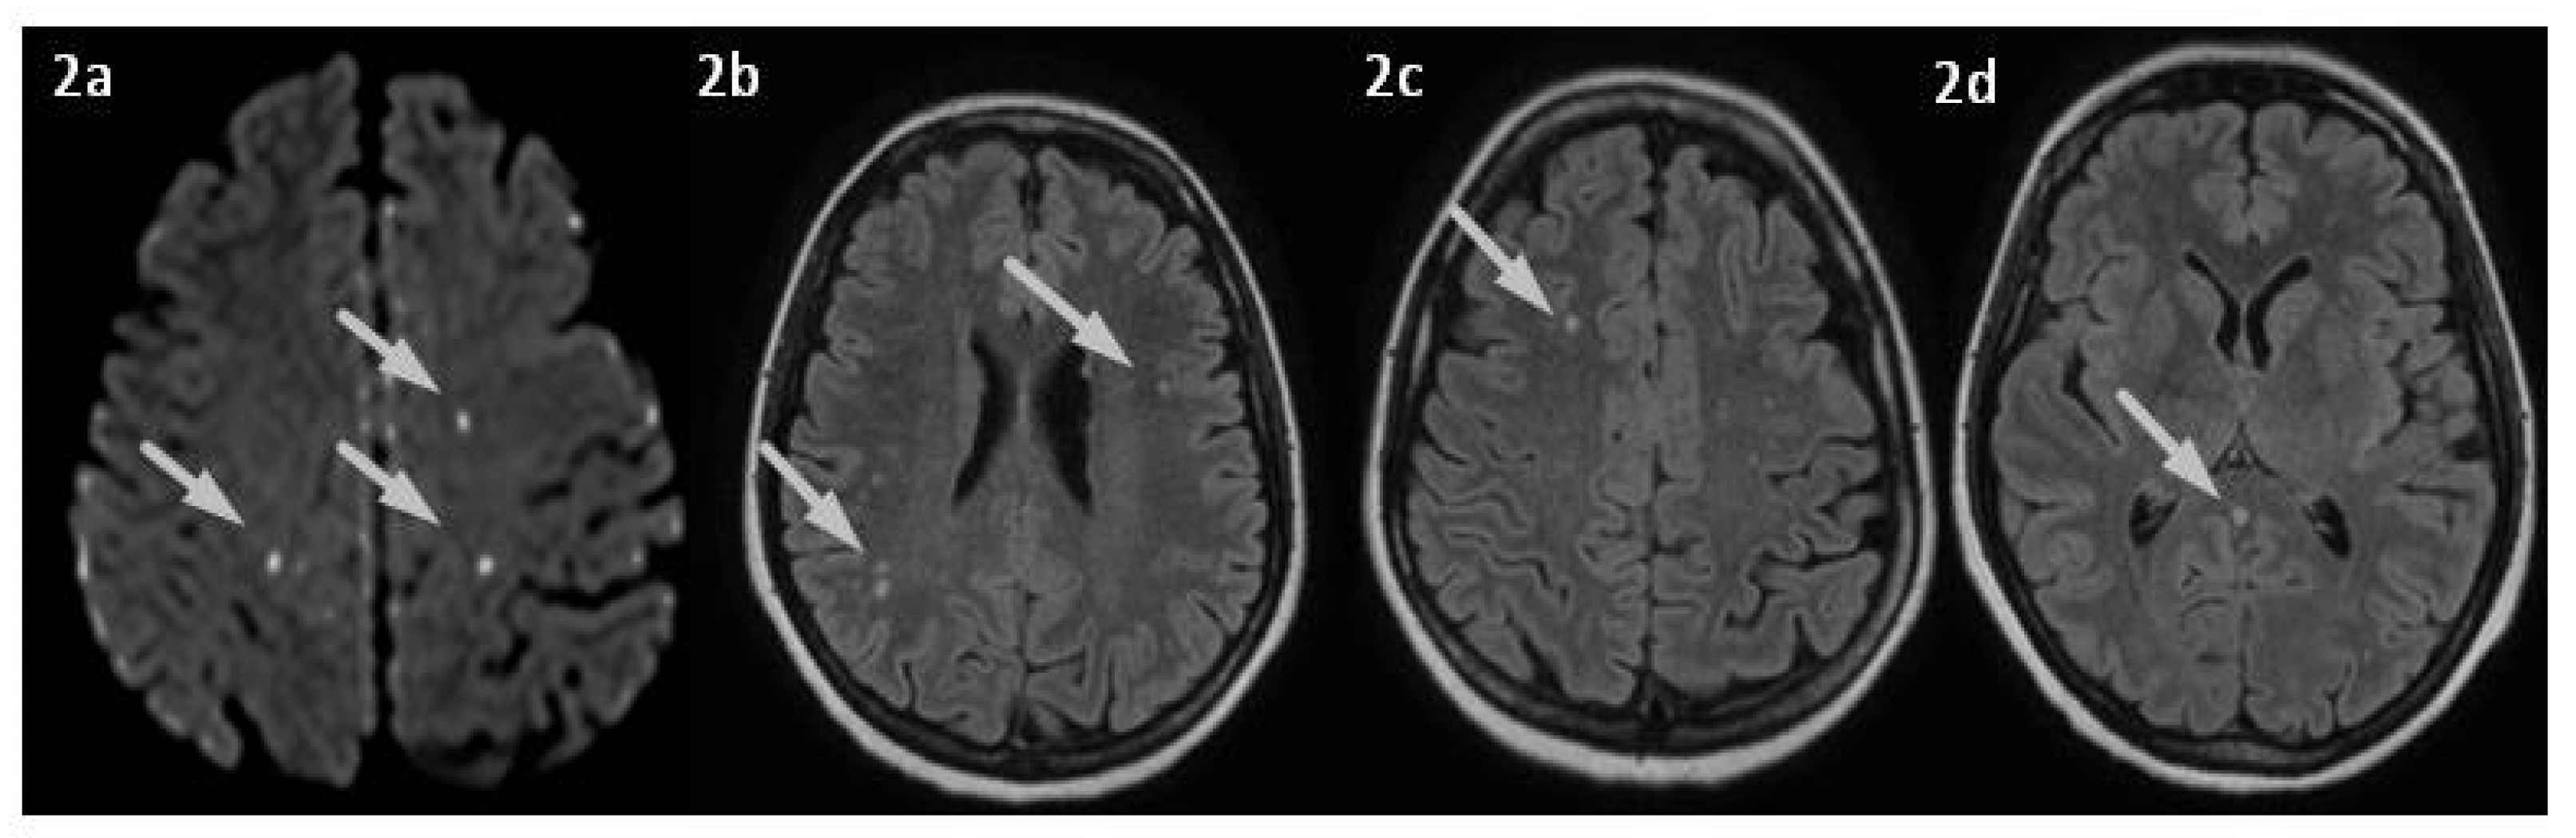

2. Case Presentation